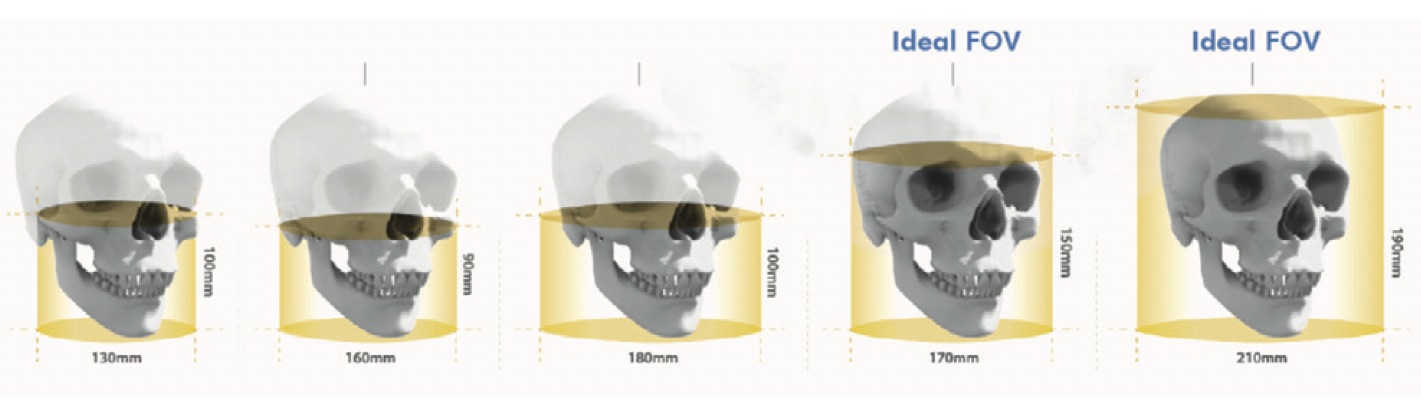

En outre, dans un appareil CBCT le faisceau de rayons X est de forme conique et produit un volume de données cylindrique ou sphérique, appelé FOV (field of view). La taille du FOV diffère selon les scanners. Certains sont capables de capturer l'intégralité du squelette maxillo-facial. De plus, certaines machines CBCT peuvent ajuster la hauteur du FOV cylindrique pour capturer une seule zone, permettant ainsi de réduire l'exposition du patient aux radiations.

Schéma montrant les différentes tailles de FOV en CBCT.

En fonction du FOV, nous pouvons classer les équipements CBCT en système à grand FOV (15-30,5 cm) et en système à FOV limité (4 à 8 cm). Ceci est important car :

Plus le FOV est élevé, plus nous avons :

- Une image agrandie de la zone anatomique

- Une plus grande exposition aux radiations

- Une résolution réduite des images

Plus le FOV est faible, plus nous avons :

- Une image d'une petite partie de la zone anatomique

- Une plus faible exposition aux radiations

- Des images à haute résolution

Si vous êtes à la recherche d'un scanner qui n'exige pas une précision maximale des structures, mais plutôt une représentation significative de la tête (comme pour l'orthodontie ou la planification des implants), un scanner CBCT à FOV large ou modéré est plus avantageux. Mais, par exemple, lorsqu'un diagnostic d'altérations dentaires est nécessaire, il faut une image plus précise d'une petite partie et dans ce cas, l'utilisation d'un CBCT à FOV limité est plus appropriée. Examinons de plus près les différentes applications d'un scanner CBCT dans un cabinet dentaire :